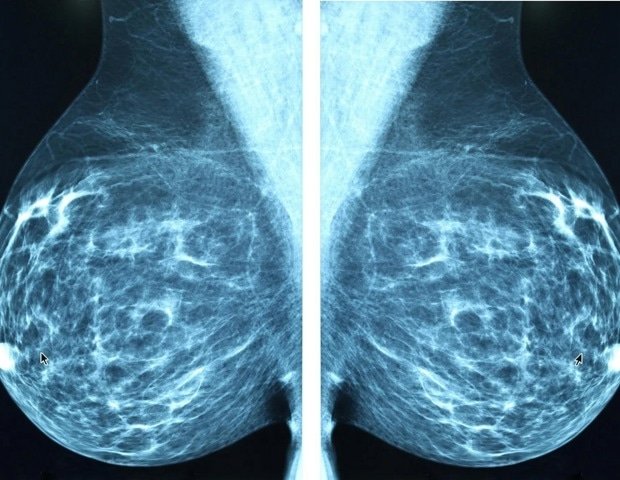

An experimental drug targeting triple-negative breast cancer overwhelms cancer cells with toxic fats, according to a new study of human tumors in mice. Triple-negative breast cancer lacks three common drug targets, making it one of the most aggressive types of breast cancer.

In this study, researchers transplanted human triple-negative breast cancer tumors into mice and treated them with DH20931. The drug significantly slowed tumor growth without causing significant weight loss or signs of toxicity in the animals. Separate laboratory experiments also showed activity against other breast cancer subtypes.